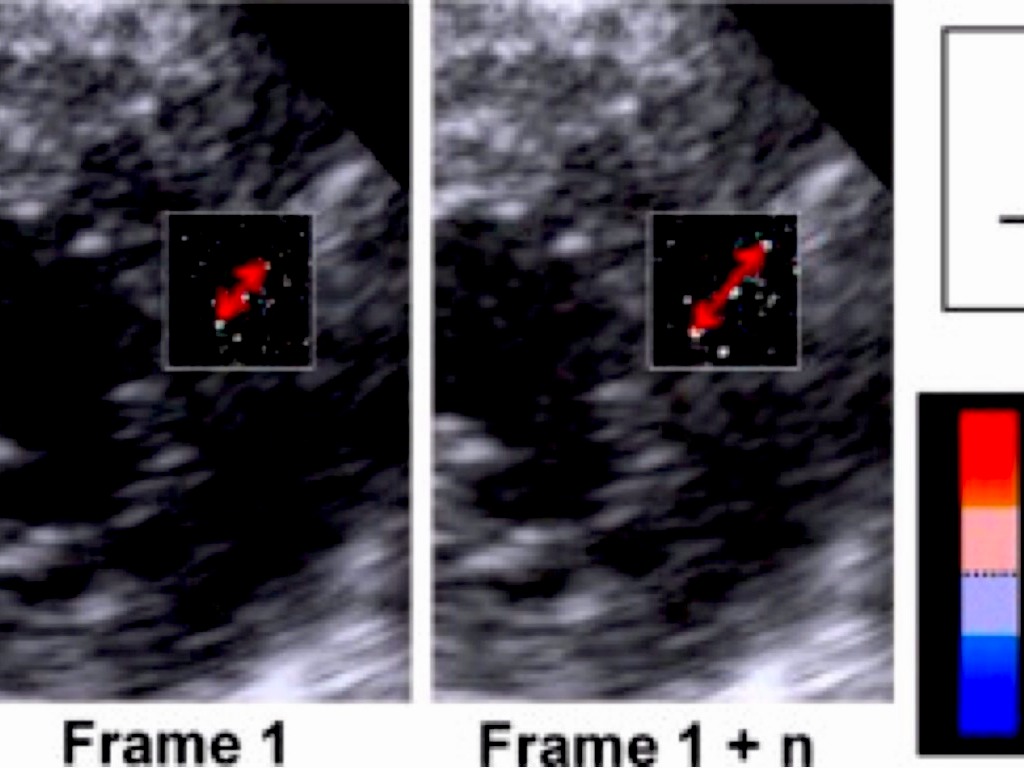

APLICAÇÃO DO STRAIN E STRAIN RATE NO DIAGNÓSTICO E MANEJO DA MIOCARDIOPATIA ISQUÊMICA

Georgia Rocha - MTDIC 4ª EDIÇÃO - Fev. 2014